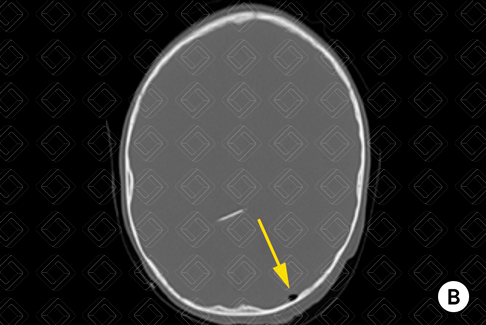

Descrição das imagens: Tomografia computadorizada do crânio: reconstruções na janela óssea (A e B) e parênquima encefálico (C). Exame realizado no paciente após troca do cateter de derivação ventricular, mostrando pequeno pneumoencéfalo (setas amarelas) adjacente à inserção do cateter. Observa-se a presença dos cateteres de derivação ventriculares (seta vermelha).

Pneumoencéfalo: Presença de ar intracraniano, de fácil reconhecimento nos exames de imagem. Na maioria dos casos, são observados no contexto de trauma ou pós-operatórios.

• Tomografia computadorizada do crânio: Conteúdo gasoso apresenta densidade muito baixa na TC (inferior a 1000 UH);